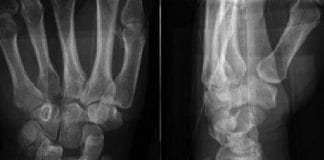

Radial Styloid Kırığı Akıl Kartı

Elin radial kenarına uygulanan direkt travmalar sonucunda, radial stiloid bölgede transvers veya oblik şekilde oluşan eklem içi kırık tipidir. AP grafide radius stiloidinin altında...

Smith Kırığı

İlk olarak İrlandalı doktor Robert William Smith tarafından 1847 yılında tanımlanmıştır. Smith kırığı, distal radiusun volar (avuç içi) yöne açılanan kırığıdır. Muayenede el bileği...

Colles Kırığı

Distal radius kırıkları genellikle el açık vaziyette yere düşme sonucu radiusun dorsale (el sırtına doğru) açılanması ile oluşur. Metafiz bölümünde oluşan basit tarzdaki kırıklardan,...